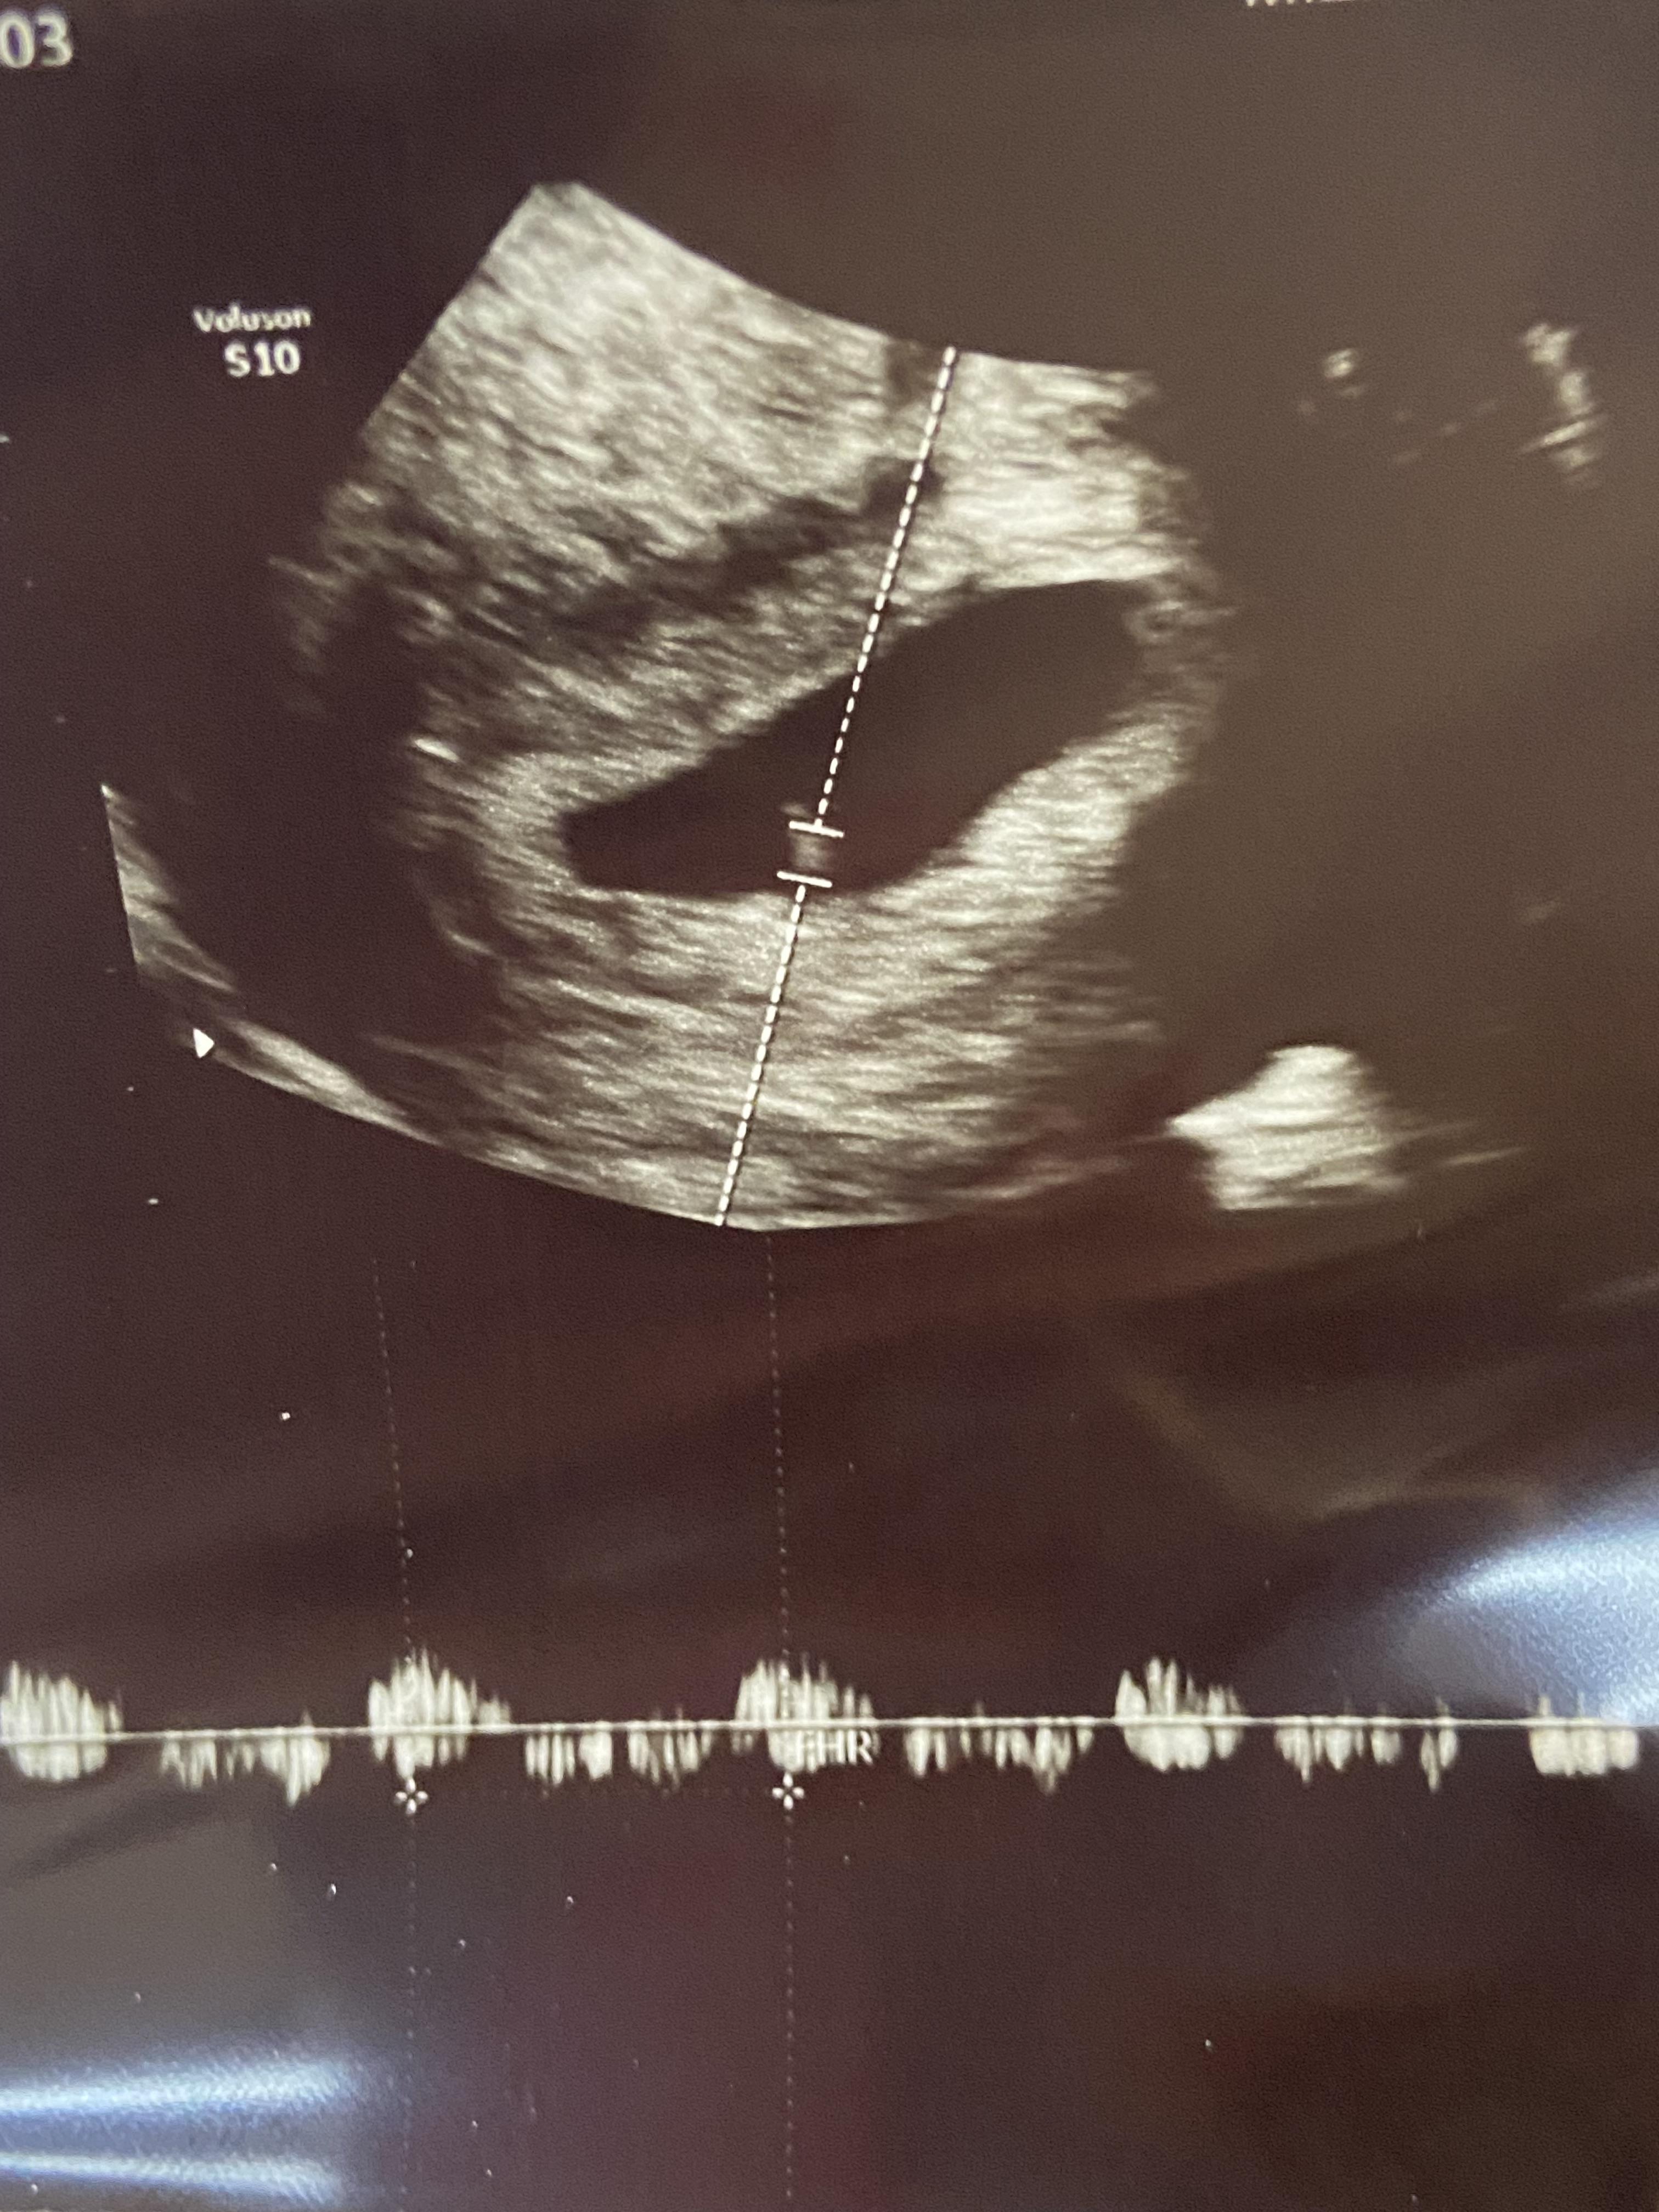

역시나 이번에도 질초음파! 혹시나 배 초음파를 할까 기대를 했지만 초기 9주이내는 질초음파로 보는 경우가 많다고 한다. 내 친구는( 나랑 주수 비슷) 배 초음파로 했다고 해서 부러웠음...

이번에는 아기집와 강낭콩까지 볼 수 있었다. 심장소리도 들음!!! 120bpm으로 뛰는 심장소리... 너무 신기했다. 자궁의 크기를 보시고는 7주차라고 하셨다. 확인을 하고 나니 드디어! 임신확인서와 산모수첩을 받았다!!!!!!!